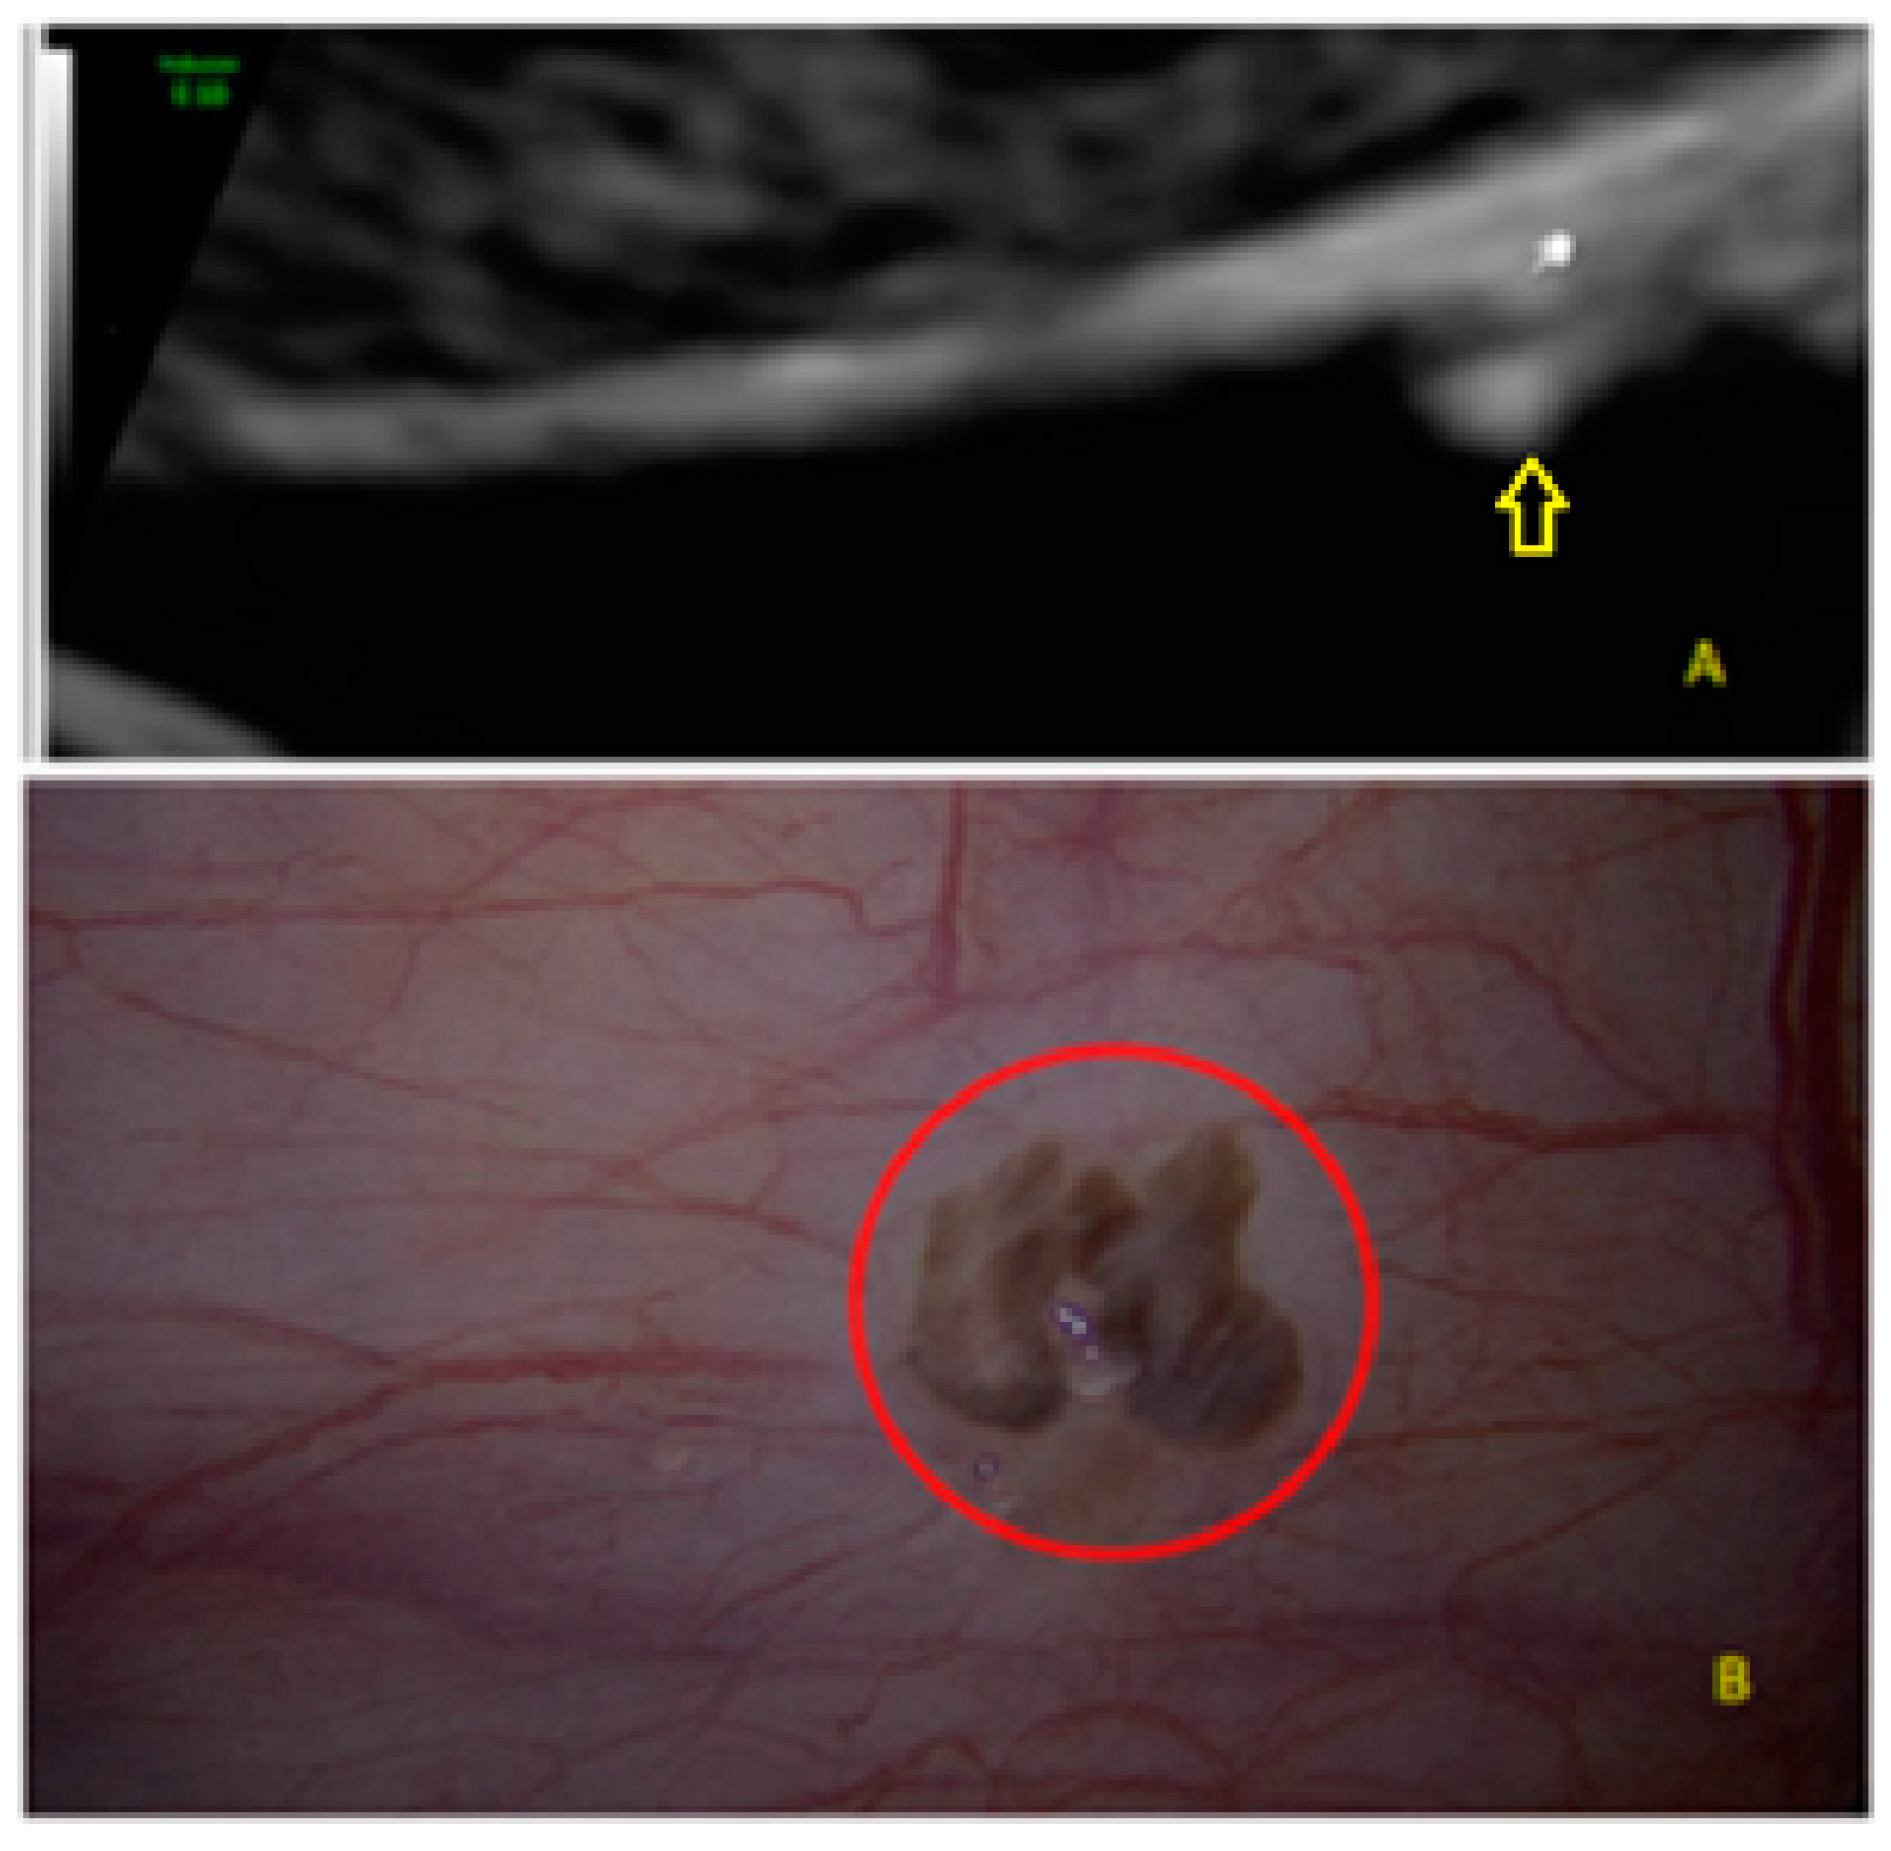

- The presence of hypoechogenic associated tissue (hypoechoic areas surrounding a small cyst area; we called this a “hat”). This tissue does not protrude or invaginate the peritoneal surface.

- The lesion may be convex, protruding from the peritoneal surface into the peritoneal cavity (we called this “bulging”), or it may appear as a concave defect in the peritoneum (we called this a “pocket”).

- The presence of hyperechoic foci (we called this a “pearl”).

- The presence of velamentous (filmy) adhesions associated to the lesion (we called this a “veil”).

3.2. Cystic Multiple Separate Lesions